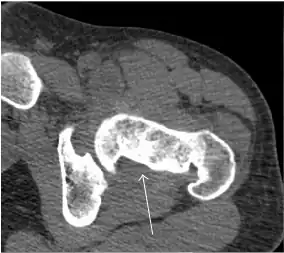

MRI has been shown to have 100% sensitivity and specificity in prospective studies of occult hip fractures. These fractures were diagnosed by bone marrow edema and a low signal fracture line, mainly on T1 or T2 weighted images (Figure 10).[1]

Figure 10:

-

Stress femoral neck fracture in a young athlete barely visible in X-ray film as a sclerotic line (arrow)[1] -

In this case, Tc 99 scintigraphy shows a band of uptake[1] -

Furthermore, T1 (left) and DP fat saturated (right) weighted MR images showed the fracture line and a pattern of edema.[1]

Nuclear Medicine

Bone scanning in people with hip pain can be complementary to other imaging studies, mainly in indeterminate bone lesions to clarify whether it is an active lesion with abnormal radiotracer accumulation. Nevertheless, MRI has replaced scintigraphy in the diagnosis of most of these conditions. An example is stress or insufficiency fractures: increased uptake is usually present in around 80% of fractures within 24 h, and 95% of fractures reveal activity by 72 h following trauma, showing an overall sensitivity of 93% and specificity of 95%. MRI is superior to bone scans in terms of sensitivity (99%-100%) and specificity (100%). Moreover, a bone scan does not provide detailed anatomical location of the fracture, and further imaging is usually required.[1]